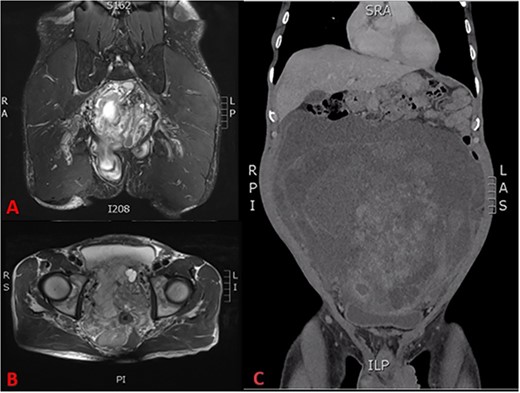

His full blood count, biochemistry, inflammatory, and tumour markers were within the normal range. The CT scan revealed a large pelvic extraperitoneal mass displacing bowels with heterogenous enhancing solid and non-enhancing cystic components (Fig. 2C). MRI evaluation of the pelvis showed a heterogenous and hyperintense lesion with internal septation and cystic changes invading the pelvic floor (Fig. 2A, B).

(A) T2 coronal section of MRI pelvis showing tumour invasion of the pelvic floor, (B) T2 axial MRI pelvis showing tumour involvement of the left seminal vesicle and, (C) coronal CT scan showing compression of the bladder and tumour burden.